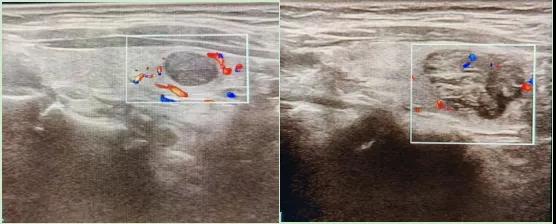

彩色血流顯示:用紅藍(lán)色標(biāo)記血流信號(hào),區(qū)分腫瘤的供血情況。

1.形態(tài):良性多呈圓形,邊界清晰;惡性可能不規(guī)則、邊緣模糊。

2.回聲:低回聲結(jié)節(jié)風(fēng)險(xiǎn)較高(像“烏云”一樣暗)。

3.鈣化:細(xì)小砂礫樣鈣化提示惡性可能。

4.血流信號(hào):惡性結(jié)節(jié)常有豐富紊亂的血流。